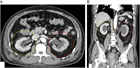

1. 片側の腰背部痛や側腹部痛では水腎症を念頭に置き、まず超音波検査を行い、尿路閉塞の位置と原因を同定するには単純CTを撮影する。